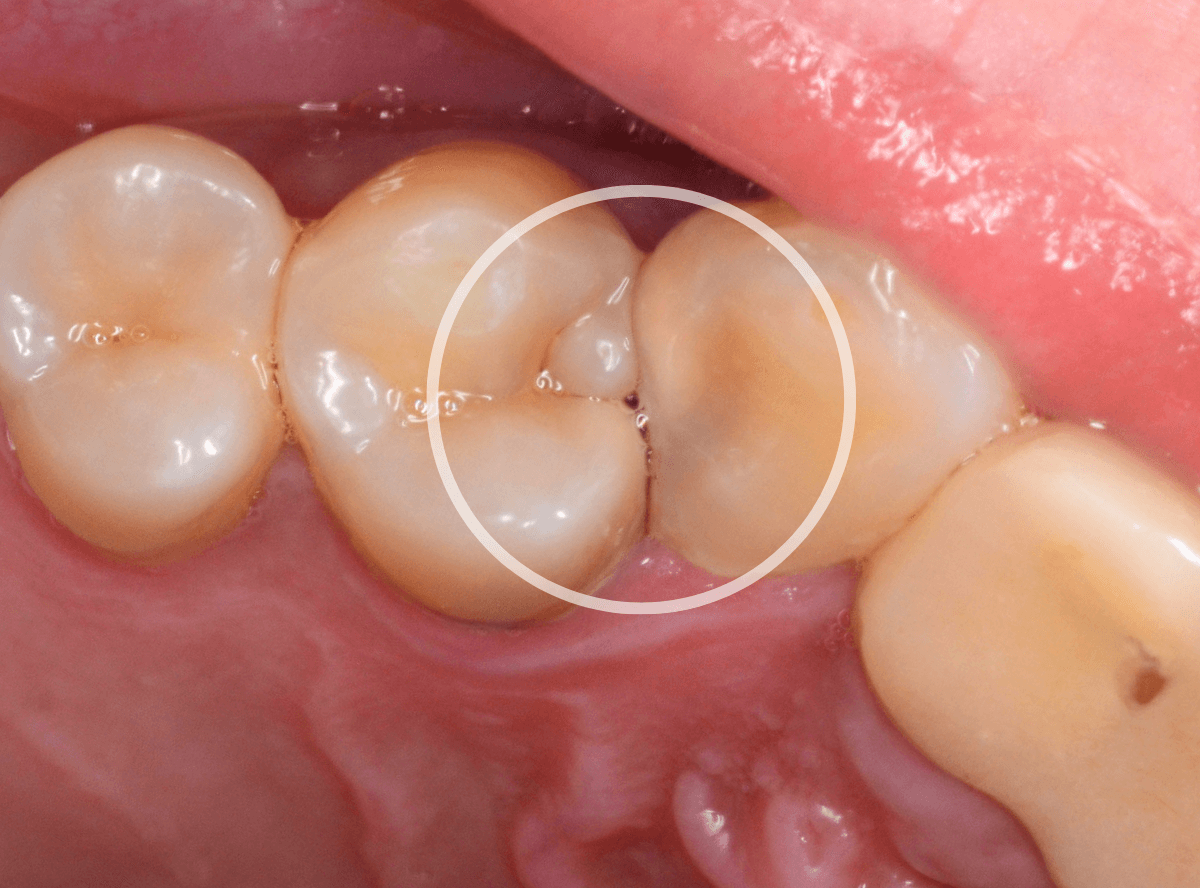

Case.25 レントゲン所見と目視を頼りに、虫歯治療

検査時に〇部、歯と歯の間の小臼歯部に虫歯らしき黒い影があるのが見つかりました。

かなり怪しいですが、メタル・インレーが入ってるので、それが透けている可能性もあります。

レントゲン写真で確認します。

レントゲンでは後ろの大臼歯部の方が虫歯になっているように見え、小臼歯部は問題ないように見えます。